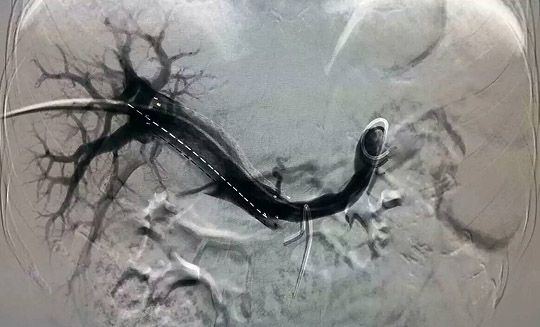

—腫瘤一科成功開(kāi)展山東省首例支架+碘125粒子條治療門(mén)靜脈主干癌栓

2015年11月27日,在復(fù)旦大學(xué)附屬中山醫(yī)院介入科羅建鈞教授指導(dǎo)下,腫瘤一科張開(kāi)賢主任帶領(lǐng)吳林霖、邢超、楊森等年輕醫(yī)生組成的介入團(tuán)隊(duì),成功地對(duì)一例原發(fā)性肝癌并門(mén)靜脈主干癌栓的患者實(shí)施了山東省首例支架+碘125-粒子條+肝動(dòng)脈栓塞化療術(shù),術(shù)后患者情況良好,目前正在進(jìn)一步康復(fù)中。

門(mén)靜脈癌栓治療方法眾多,其中支架+碘125粒子條植入是近年來(lái)應(yīng)用的一種新方法。支架可迅速開(kāi)通門(mén)靜脈,恢復(fù)向肝血流,緩解門(mén)靜脈高壓,使肝功能恢復(fù)正常,但普通支架由于只有機(jī)械擴(kuò)張作用而沒(méi)有抗腫瘤作用,術(shù)后很容易導(dǎo)致門(mén)靜脈堵塞,為解決這一難題,在植入門(mén)靜脈支架的同時(shí)植入碘125-粒子條,利用碘125放射性粒子發(fā)出的低能量伽馬射線持續(xù)殺傷腫瘤細(xì)胞,有效控制腫瘤生長(zhǎng),防止門(mén)靜脈再次堵塞,預(yù)防或推遲門(mén)靜脈再狹窄的發(fā)生,使門(mén)靜脈長(zhǎng)時(shí)間保持通暢,為后續(xù)栓塞化療、消融治療等贏得時(shí)間,從而延長(zhǎng)肝癌患者的生存期。